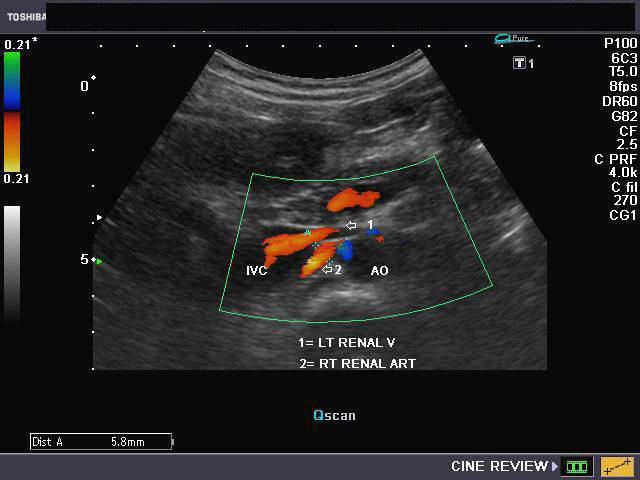

The above 4 ultrasound and Color Doppler images show the origin of the normal right renal artery from the abdominal aorta (Ao), just below the origin of the superior mesenteric artery. It takes careful adjustment of the wall filter settings to remove the motion artifacts from the aortic pulsations, with appropriate PRF settings to get a decent Color Flow image of the Right renal artery. The right renal artery is seen coursing behind the IVC (Inferior Vena Cava) after a antero-lateral origin from the Aorta (Ao). The left renal vein is also seen traversing anterior to the abdominal aorta (Ao) and between it and the SMA (superior Mesenteric Artery). All the above 4 images are transverse sections through the epigastrium. The liver provides a good window to view these vessels.